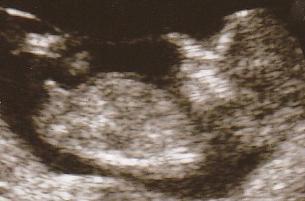

هاذي صورتين لبنت و ولد بلاسبوع بين ال11 الى اال13

هاذا الولد

شفتي كيف عضوه منتصب لفوق بالنسب للعمود الفقري وهاذا الي بيكون القضييييب